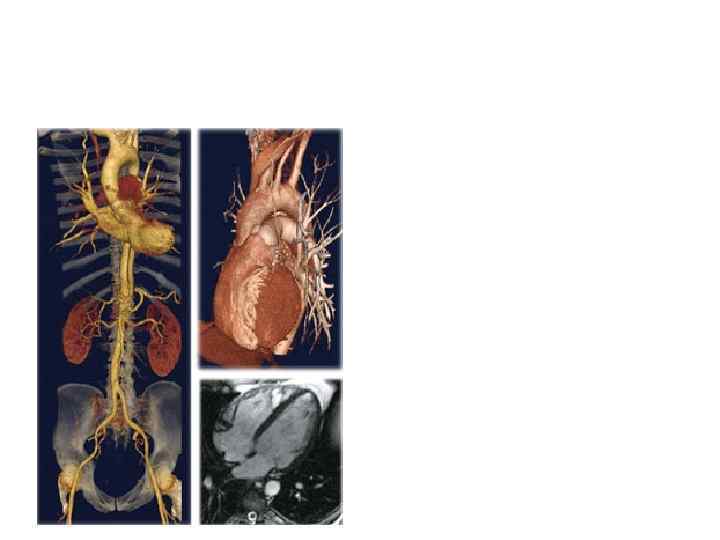

VR (объемный рендеринг) реконструкция сосудов. • Аневризматиче ское расширение аорты (красные стрелки). Сужение нижней мезентериальн ой артерии в результате компрессии сосуда аневризмой аорты (желтая стрелка).

МСКТ • VR (объемный рендеринг) реконструкция сосудов нижних конечностей. • Стенозы бедренных артерий.